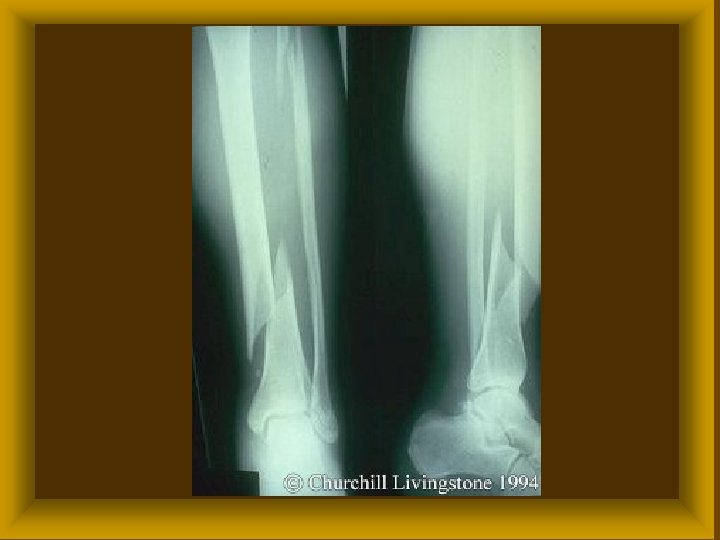

TÖRÉS ( FRACTURA ) Ø Traumás fractura * direct fractura ( behatás helyén ) * indirect fractura (behatástól távol) Ø Pathológiás fractura * tumorok, metastasisok * cysták * osteoporosis * osteomyelitis

FRACTURÁK MECHANIZMUSA ØCompressios törések ØHajlításos törések ØCsavarásos törések ØSzakításos törések

FRACTURÁK MORPHOLÓGIÁJA I ØRészleges törés * repedés ( fissura ) * megtöretés (infractio) ØTeljes törés

FRACTURÁK MORPHOLÓGIÁJA II Törési sík alapján : * haránt * hosszirányú * ferde * spirális Ø Törési darabok alapján * egyszerű * többszörös * rom törés Ø